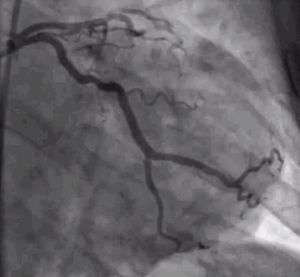

Patients without ST segment elevation are said to suffer from non-ST-elevation acute coronary syndrome and tend not to have full occlusion of a coronary artery. If there is evidence of myocardial cell death (especially elevated cardiac biomarkers) they are considered to have a non-ST-elevation myocardial infarction (NSTEMI); otherwise they are classified as suffering from unstable angina.[8] Their management is based on the estimation of their risk for adverse events. Patients at low risk can be adequately treated with medical therapy, in many ways similar to the one used for STEMI (but excluding thrombolytics). Those at moderate to high risk benefit from an early invasive strategy, which includes coronary angiography and, if necessary, revascularization with percutaneous coronary intervention or coronary artery bypass surgery.[9]

Individuals without ST segment elevation are presumed to be experiencing either unstable angina (UA) or non-ST segment elevation myocardial infarction (NSTEMI). They receive many of the same initial therapies and are often stabilized with antiplatelet drugs and anticoagulated. If their condition remains (hemodynamically) stable, they can be offered either late coronary angiography with subsequent restoration of blood flow (revascularization), or non-invasive stress testing to determine if there is significant ischemia that would benefit from revascularization. If hemodynamic instability develops in individuals with NSTEMIs, they may undergo urgent coronary angiography and subsequent revascularization. The use of thrombolytic agents is contraindicated in this patient subset, however.[53]